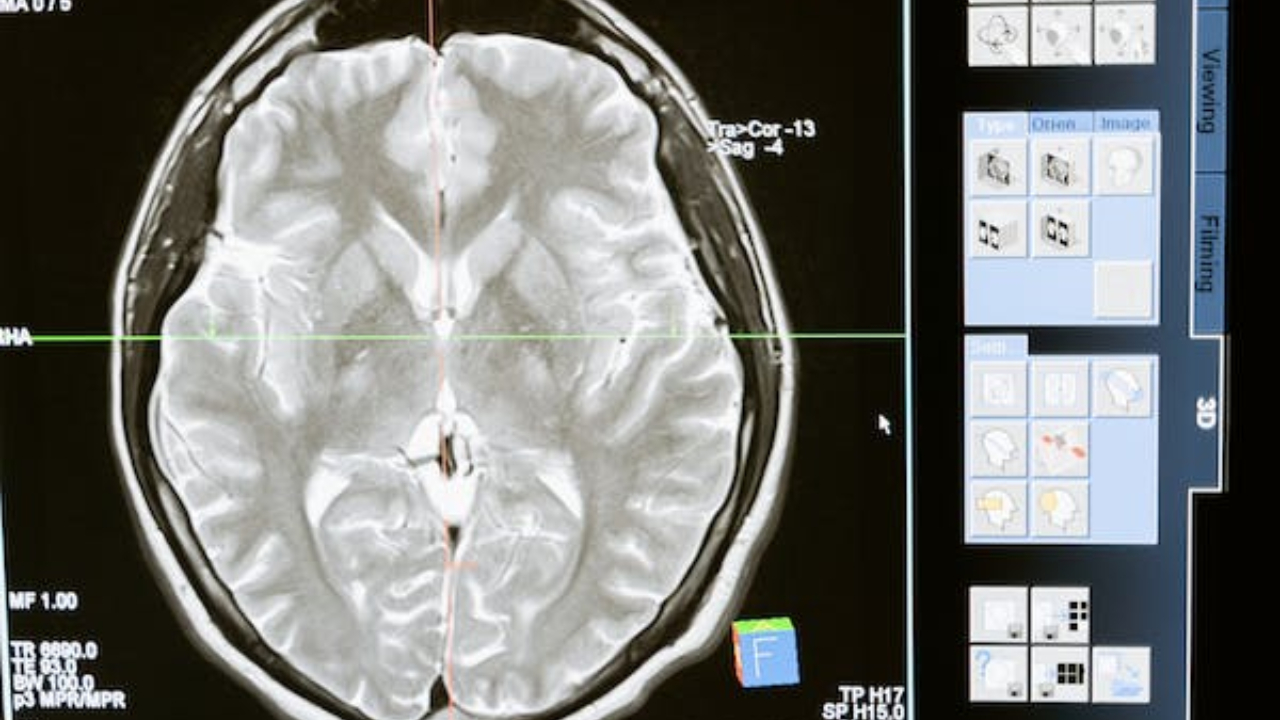

Pick hastalığının tanısı genellikle nörolojik muayene, bilişsel testler ve görüntüleme çalışmalarıyla konulur. Ancak, hastalığın kesin tanısı, otopsi sonuçlarına dayanmaktadır. Maalesef, şu anda Pick hastalığı için etkili bir tedavi bulunmamakla birlikte, semptomların yönetimi ve hastanın yaşam kalitesini artırmaya yönelik destekleyici tedaviler uygulanabilir.